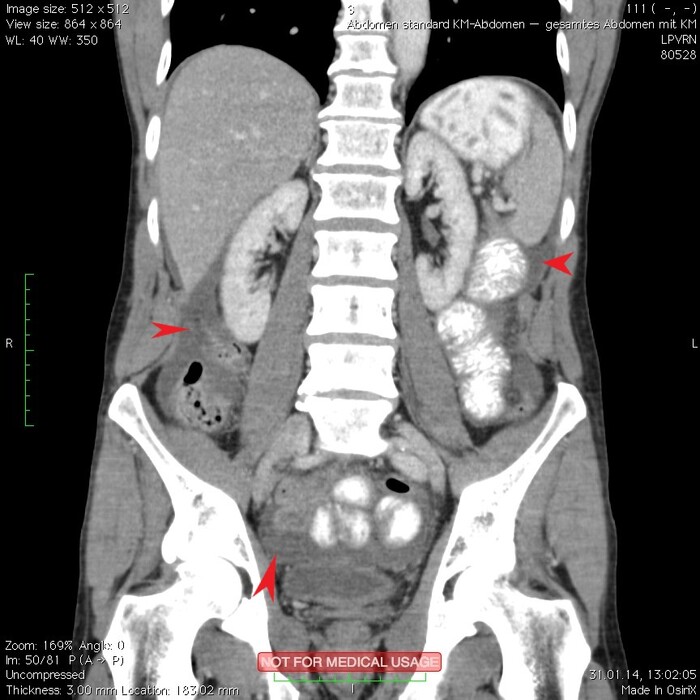

Мужчина, 32 года. Во время игры в футбол получил удар в низ живота, игру продолжил. Впоследствии боли в животе усиливались, стали нестерпимыми, ухудшилось общее самочувствие. На следующий день после игры пошёл сдаваться в больницу. Хирурги клинически описывают разлитой перитонит (воспаление брюшины) и отсылают пациента к нам на КТ, которое мы провели с внутривенной дачей контраста + заставили контраст ещё выпить (специальный раствор для перорального применения).

Так как клиника у нас острого живота после тупой травмы, учитывая что боли во всём животе и признаков большой кровопотери нет, то первое, что ищем - это свободный газ в брюшной полости, и находим его! (для этого лучше всего подходит т.н. лёгочное окно, как представлено ниже, или можно искать в костном окне - это спец.настройки яркости и контраста для просмотра разных структур тела - лёгкие, мозг, мягкие ткани, кости):

Отмечаем про себя, что в верхних квадрантах свободного газа не так уж и много. При перфорации желудка газа намного больше. Также выясняем, что газ есть также и в нижних квадрантах:

Ещё бросается в глаза массивный выпот (стрелки) во всех этажах, а также утолщение брюшины на всём протяжении, что указывает на диффузный (разлитой) перитонит. Тут, кстати, уже мягкотканное окно:

Итак, имеет место быть свободный газ в брюшной полости + свободная жидкость + перитонит. Определённо перфорация! Осталось найти источник. Желудок не подходит по механизму, а точнее по локализации травмы. Мочевой пузырь - в нём нет воздуха. Остаётся методом исключения только кишечник. Толстый или тонкий? Явно не верхние отделы толстого кишечника (ободочная кишка в области печеночного и селезеночного углов, а также поперечная исключаются - было бы больше воздуха). Сигма и нисходящая тоже заполнены стулом и воздухом. Получается, что тонкий кишечник всему виной.

Верхние (проксимальные) отделы точно не причём. Жидкость (звёздочки) больше в малом тазу, тут же и воздух. Для сравнения верхний этаж:

Hижний этаж:

И тут СТОП! А это чтo такое???

Кишке это точно не принадлежит, как ни крути. Это вышедший за пределы кишки контраст, который пациент выпил!

Осталось только место выхода найти:

Итого: перфорация тощей кишки в дистальных отделах, разлитой перитонит.

Был успешно прооперирован, место перфорации ушито, выписан.